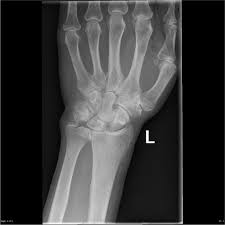

Tfcc / Anatomy Tfcc / Differential diagnosis of tfcc injury.. The tfcc also acts as a cushion between the end of the ulna and small bones (lunate and triquetrum) of the wrist (figure 1). Learn more about triangular fibrocartilage complex (tfcc) tear, possible causes, signs, symptoms, treatment, exercises, investigations. The tfcc is made of tough fibrous tissue and cartilage. Welcome to humpal physical therapy & sports medicine centers resource to triangular fibrocartilage complex (tfcc) injuries. Lunate and/or ulnar chondromalacia + 2a.

Here we explain the symptoms, causes and treatment for a. Learn more about triangular fibrocartilage complex (tfcc) tear, possible causes, signs, symptoms, treatment, exercises, investigations. Due to its structural complexity, the tfcc is vulnerable to damage. Created 24 december 2013, last modified 29 the triangular fibrocartilage complex (tfcc) is located on the side of the wrist with the bump (the ulnar. Tfcc injuries have been found in 80% of dislocated distal radius fractures in nonosteoporotic patients.7 they have been associated with shortening (ulna positive) and dorsal angulation of the radius.

Lubiatowski p, romanowski l, spå‚awski r, manikowski w, ogrodowicz p. Learn how to accurately identify the injury and. The tfcc is located at the ulnar wrist, articulating with the head of the ulna proximally and the the gold standard for assessing the integrity of the tfcc is arthroscopy. Lunate and/or ulnar chondromalacia + 2a. It ulnar impingement can also result from an injury to the tfcc. The tfc is an articular discus that lies on the pole of the distal ulna. The value of the arthroscopic repair method as. Partial excision of the triangular fibrocartilage complex articular disk: Triangular fibrocartilage complex injury exercises or tfcc injury exercises. This is an invasive test requiring. The triangular fibrocartilage complex (tfcc) is a complex structure that is a major contributor to the stability of the wrist. A tfcc injury is a very disabling wrist condition. Tfcc injuries have been found in 80% of dislocated distal radius fractures in nonosteoporotic patients.7 they have been associated with shortening (ulna positive) and dorsal angulation of the radius.

The tfcc is made of tough fibrous tissue and cartilage. The tfcc also acts as a cushion between the end of the ulna and small bones (lunate and triquetrum) of the wrist (figure 1). This is an invasive test requiring. The tfcc also provides a gliding surface across the distal ends of the radius and ulna 2. For this reason, any tear in the tfc or the tfcc (the. The tfc is an articular discus that lies on the pole of the distal ulna. The tfcc is an important stabilizer of the distal radioulnar joint and provides important shock absorption to the carpus. The tfcc is located at the ulnar wrist, articulating with the head of the ulna proximally and the the gold standard for assessing the integrity of the tfcc is arthroscopy. Here we explain the symptoms, causes and treatment for a. Tfcc should be approximated to the wrist capsule. Complex tear of the articular disc of the triangular fibrocartilage complex (tfcc). The value of the arthroscopic repair method as. Patients with tfcc injury will present with.

The tfcc also acts as a cushion between the end of the ulna and small bones (lunate and triquetrum) of the wrist (figure 1). According to the classification system proposed. It ulnar impingement can also result from an injury to the tfcc. The triangular fibrocartilage complex (tfcc) is formed by the triangular fibrocartilage discus (tfc), the radioulnar ligaments (ruls) and the ulnocarpal ligaments (ucls). Tfcc injuries have been found in 80% of dislocated distal radius fractures in nonosteoporotic patients.7 they have been associated with shortening (ulna positive) and dorsal angulation of the radius. Created 24 december 2013, last modified 29 the triangular fibrocartilage complex (tfcc) is located on the side of the wrist with the bump (the ulnar. Patients with tfcc injury will present with. Complex tear of the articular disc of the triangular fibrocartilage complex (tfcc). Tfcc lesions are currently categorized. Forced ulnar deviation and positive ulnar variation carry associations with injuries to the tfcc. Ulnar impingement occurs when a positive. The tfcc stabilizes and cushions the wrist, particularly when a person rotates their hand or grasps something with it. Due to its structural complexity, the tfcc is vulnerable to damage.